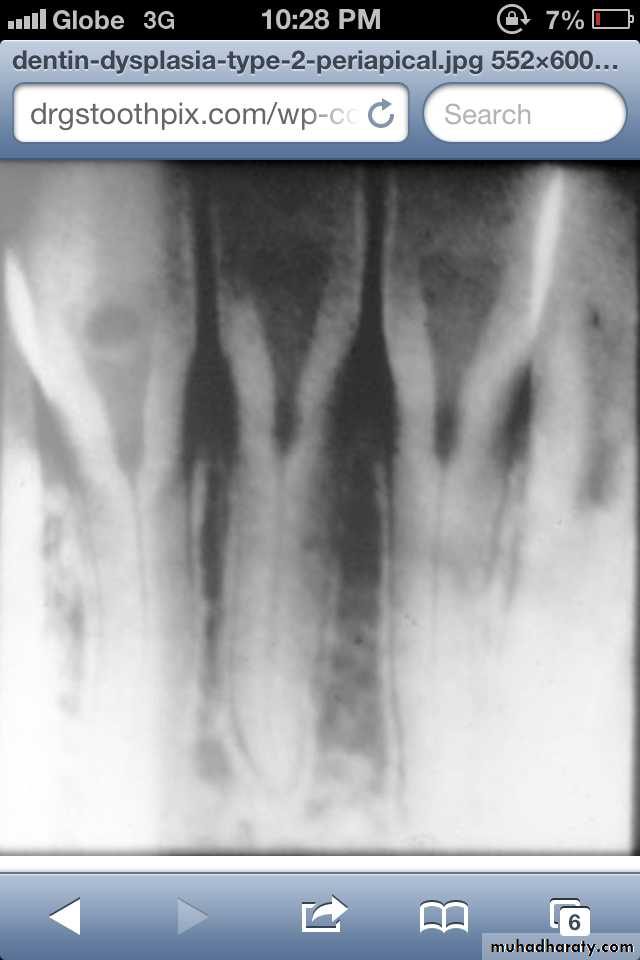

Radiographically:

Bulbous crownsCervical constriction

Thin roots

Early obliteration of roots canals & pulp chambers.

Radiographically (Type I& II ):

partial or total obliteration of pulp chambers & root canals by continued formation of dentin.

roots may be short & blunted.

Normal cementum, periodontal membrane & bone .